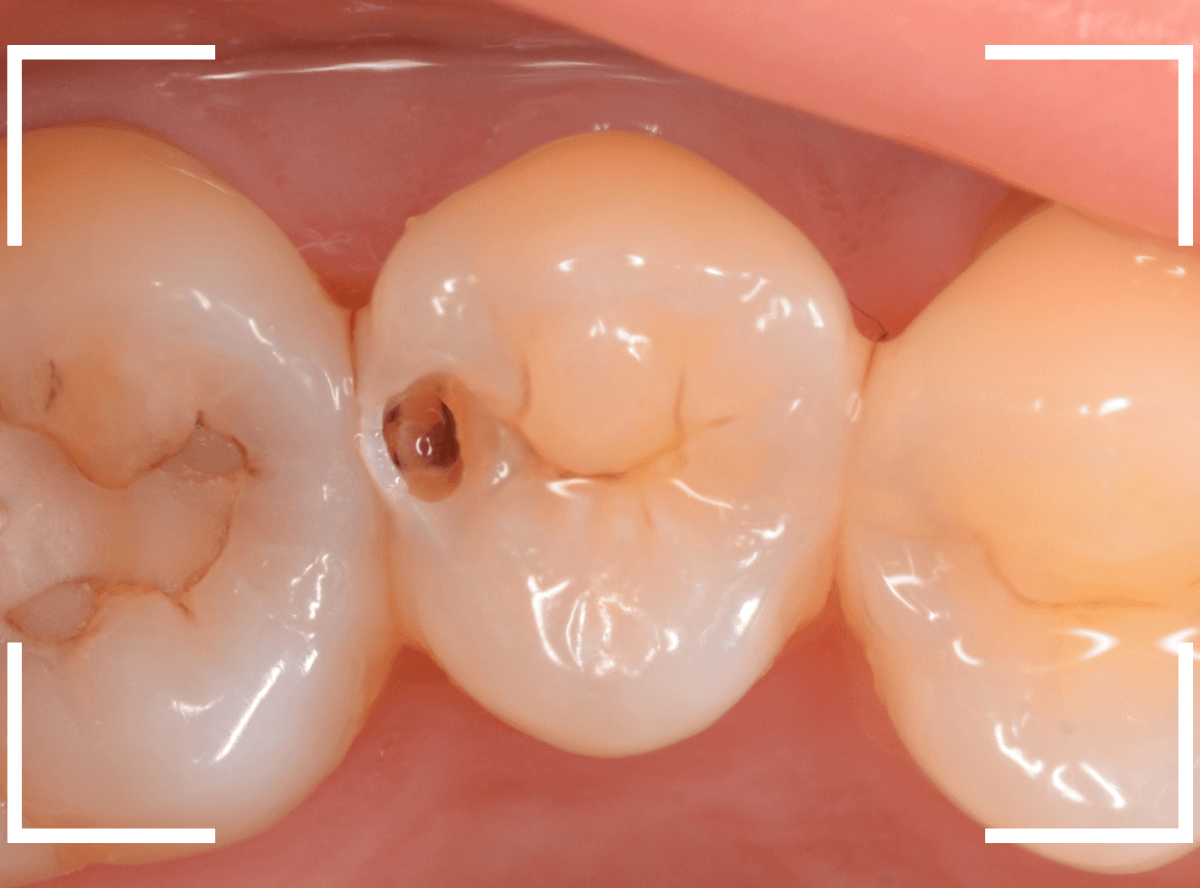

Case.7 レントゲンに写らないレジンの中の虫歯を削って調べる

こちらも定期検診希望で来院された患者さんです。

特に症状はありませんが、歯の咬頭(噛み合わせの山の部分)に小さな穴が空いていて、その周りがもやっと黒く見え、虫歯が怪しいです。

レントゲン写真で確認しますが、ここでは特に問題はなさそうに見えます。

患者さんに状況を説明し、慎重に削って調べる事になりました。

少しずつ穴の部分を削ってみると、ズブッと落とし穴にはまるような柔らかい虫歯の層(=軟化象牙質)に当たりました。

慎重に虫歯を除去したところです。

歯の溝のレジンが詰めてあった部分まで虫歯は進行していました。

とはいえ、それほど深く虫歯は進行していませんでしたので、虫歯除去後、レジンを充填して治療は終われました。

このように定期的にメンテナンスに来ていただくと虫歯が本格的に進行する前に対処する事ができます。